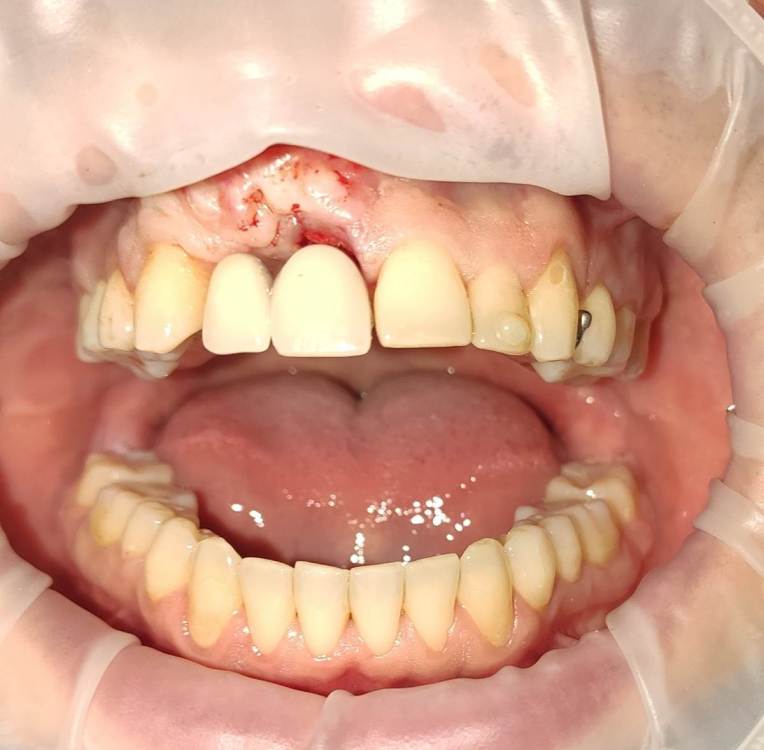

АнтонТЛТ Опубликовано 23 ноября, 2021 Поделиться Опубликовано 23 ноября, 2021 (изменено) 09.04.2021 в 10:04, red_butler сказал: @АнтонТЛТ весь кейс покажешь? Промежуточный результат Изменено 23 ноября, 2021 пользователем АнтонТЛТ 1 Ссылка на комментарий

АнтонТЛТ Опубликовано 23 ноября, 2021 Поделиться Опубликовано 23 ноября, 2021 5 минут назад, Карен Аванесов сказал: Ничего что я к Вам спиной ахаха ахахахаахах))))))))))) Антон показывай все! Фото с операции нет. Но по разрезу можно догадаться что было сделано) жду созревания, чтобы имплантироваться. Ссылка на комментарий

АнтонТЛТ Опубликовано 23 ноября, 2021 Поделиться Опубликовано 23 ноября, 2021 Вот ещё есть фотка после удаления с протезом Ссылка на комментарий